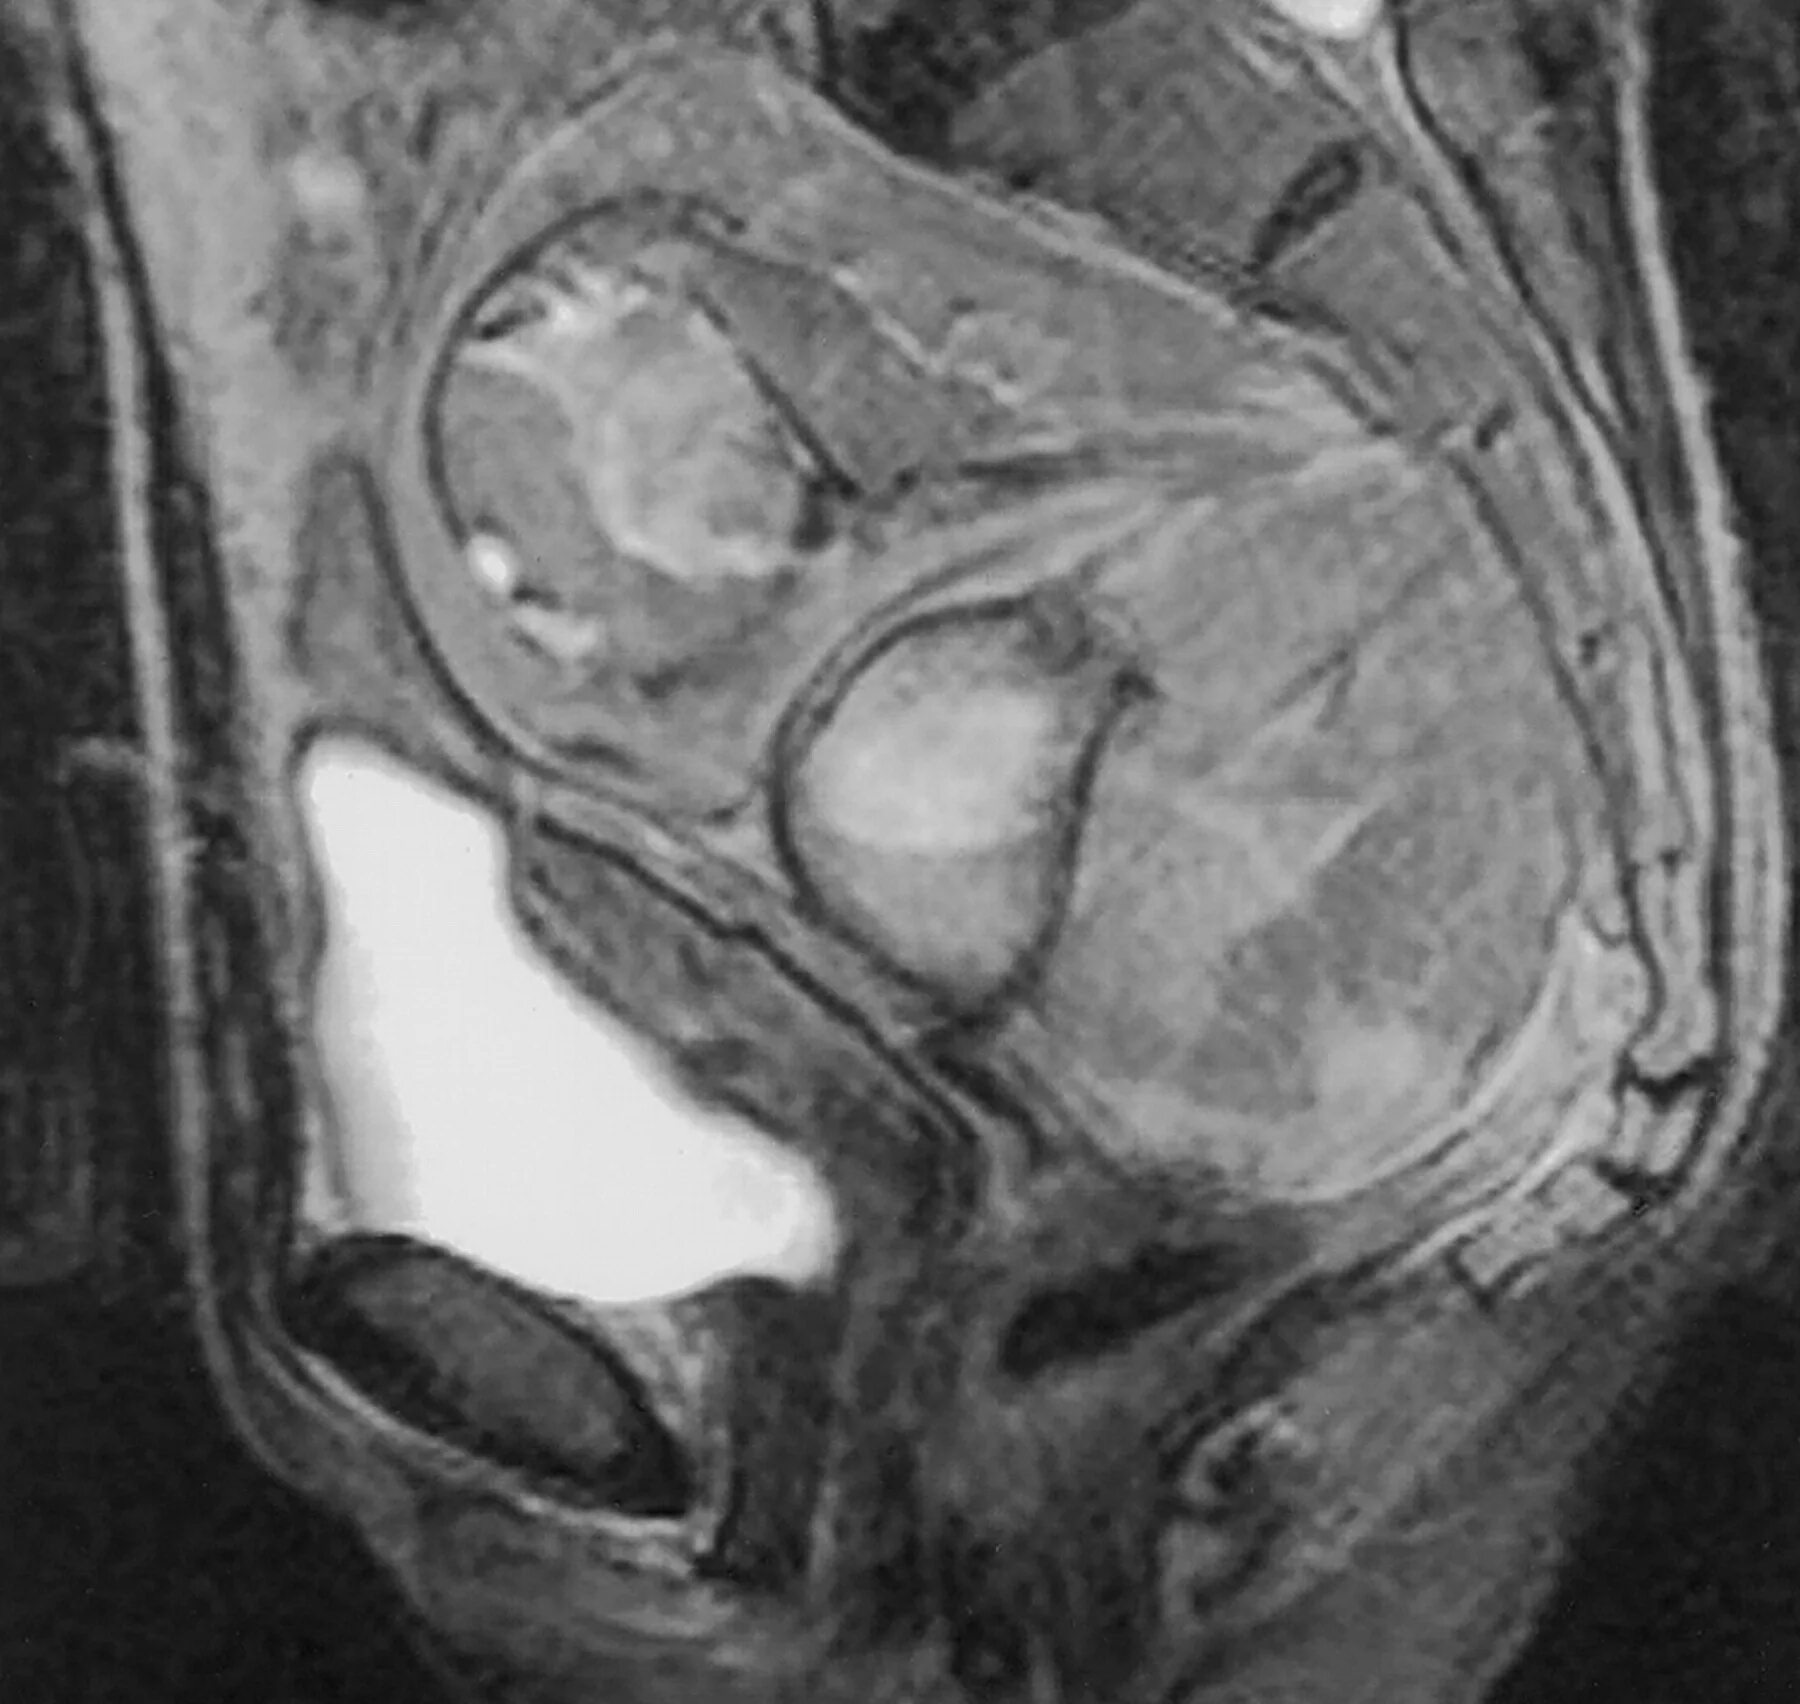

Образования малого таза мрт